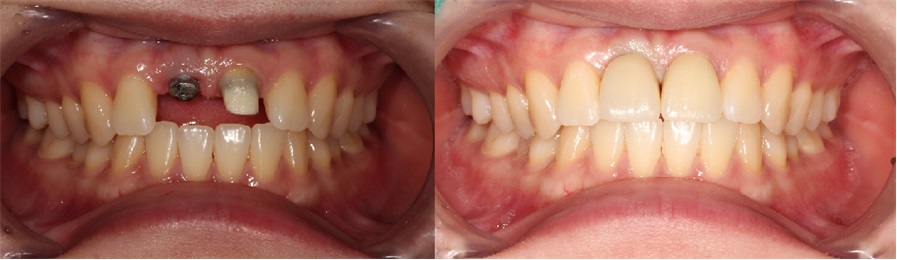

치료전후사진